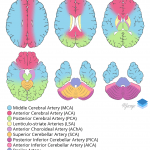

- Posterior Inferior Cerebellar Artery (PICA) Infarct